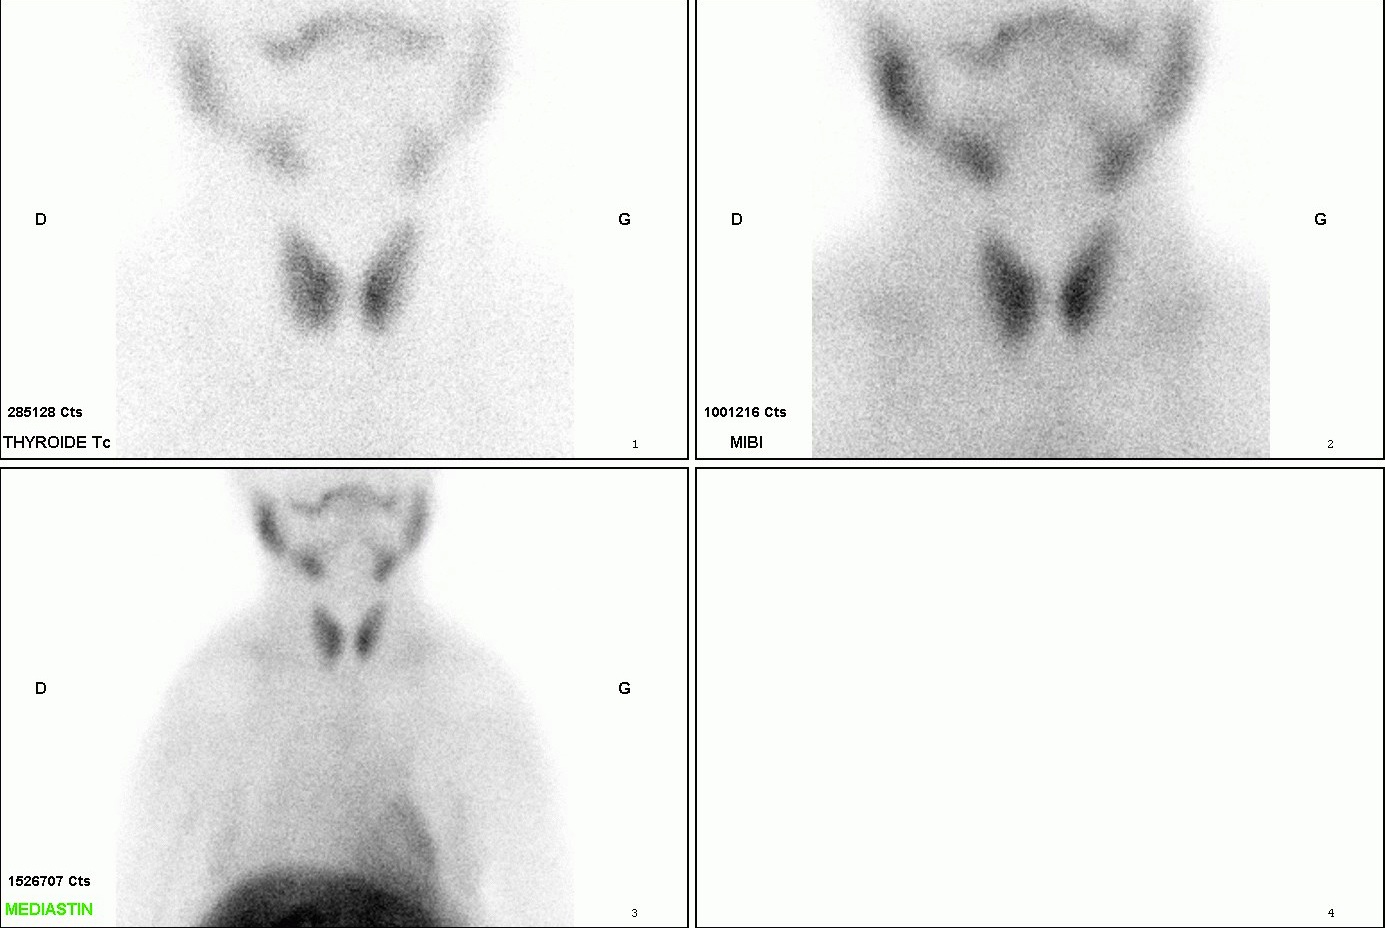

Sur les images planaires et sur les images de soustraction, mise en évidence d’une image additionnelle polaire inférieure droite.

La tomoscintigraphie couplée au scanner centrée sur la région cervico-thoracique confirme la présence d’une structure nodulaire de 12 mm de diamètre fixant le MIBI dans la région polaire inférieure droite, située contre la paroi latérale droite de la trachée.

Scintigraphie en faveur d’un adénome parathyroïdien polaire inférieur droit (P3 droite).